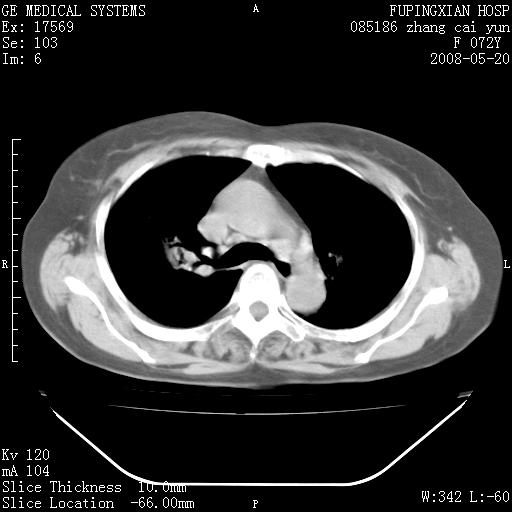

标题: CT13542:发热,咳嗽数日,经抗菌素治疗好转,请大家看排除 [打印本页]

标题: CT13542:发热,咳嗽数日,经抗菌素治疗好转,请大家看排除

上叶支气管略变窄并通畅,内壁光滑。考虑:单纯阻塞性肺炎!

右上叶支气管走行自然,未见明显管壁增厚等征像,另左主支气管起始部可见异常腔道向左侧延展左肺动脉干后方,与左下叶支气管相通,为左下叶支气管变异?

有节段性阻塞性肺炎与不张,近段支气管狭窄,周围散在肿大淋巴结影,以周围型肺癌可能性大,建议纤支镜检查。

右肺上叶实变影,内见支气管充气征,右上叶支气管通畅,肺门区未见软组织密度影,抗炎治疗有效,考虑炎症,建议继续抗炎治疗复查。

右上肺实变,间内有支气管充气征,考虑炎症,建议抗炎后复查